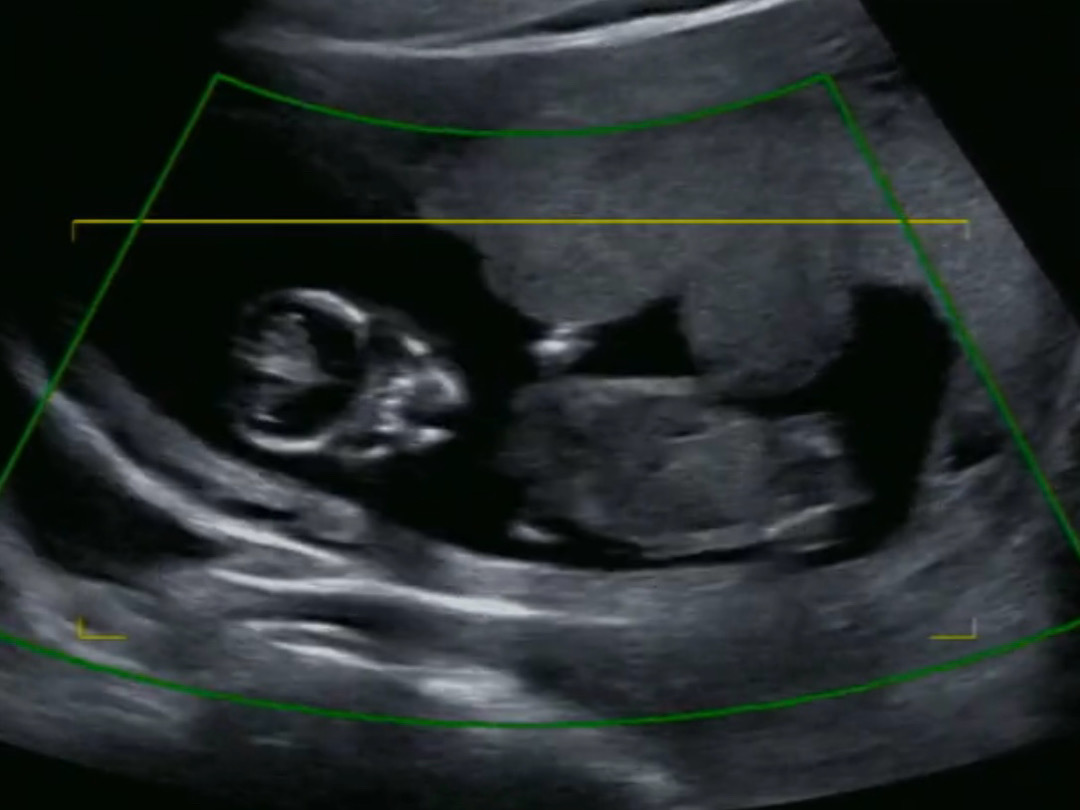

12주 해골샷~!

이 시기에는 정면으로 보면 해골같아 보인다고 하시는데 정말 해골이라서 너무 웃겼어요